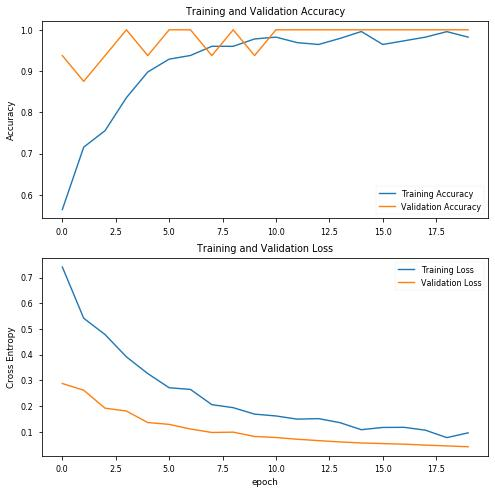

使用20个阶段和初始参数,结果看起来非常有趣,验证数据的精度达到100%!让我们绘制精度图表,评估训练的模型,并查看混淆矩阵:

precision recall f1-score support covid 0.96 1.00 0.98 27 pneumo 1.00 0.96 0.98 27 accuracy 0.98 54 macro avg 0.98 0.98 0.98 54weighted avg 0.98 0.98 0.98 54

混淆矩阵

[[27 0] [ 1 26]]acc: 0.9815sensitivity: 1.0000specificity: 0.9630

通过训练模型(初始选择超参数),我们得到:

- 100%敏感度,也就是说,对于COVID-19阳性(即真正例)的患者,我们可以在100%的概率范围内准确地确定他们为“COVID-19阳性”。

- 96%特异性,也就是说,在没有COVID-19(即真反例)的患者中,我们可以在96%的概率范围内准确地将其识别为“COVID-19阴性”。

结果完全令人满意,因为只有4%的患者没有Covid会被误诊,但与本例一样,肺炎患者和Covid-19患者之间的正确分类是最有益处的,因此我们至少应该对超参数进行一些调整,再次进行训练。

第一件事,我试图降低最初的lr一点点,然而效果并不好,所以我恢复了原值。

我还减少了数据的分割,稍微增加了Covid图像,并将最大旋转角度更改为10度,这是在与原始数据集相关的论文中建议的:

INIT_LR = 0.0001 EPOCHS = 20 BS = 16 NODES_DENSE0 = 128 DROPOUT = 0.5 MAXPOOL_SIZE = (2, 2) ROTATION_DEG = 10 SPLIT = 0.1

因此,我们有:

precision recall f1-score support covid 1.00 1.00 1.00 13 pneumo 1.00 1.00 1.00 14 accuracy 1.00 27 macro avg 1.00 1.00 1.00 27weighted avg 1.00 1.00 1.00 27

以及混淆矩阵:

[[13 0] [ 0 14]]acc: 1.0000sensitivity: 1.0000specificity: 1.0000

结果看起来更好,但我们使用了很少的测试数据!让我们保存模型,并像以前一样用大量图像对其进行测试。